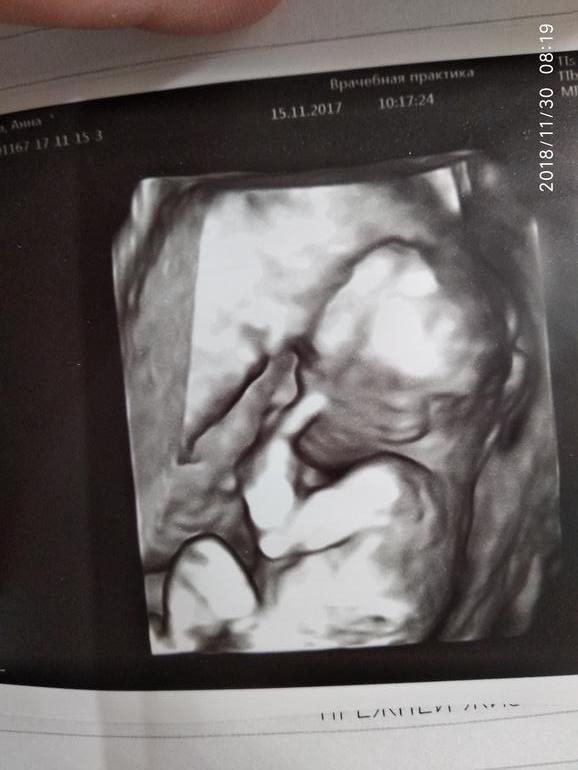

Мои УЗИ за беременность, делала почти каждую неделю, на ребенке никак не отразилось, зато я была спокойной

Сверху вниз

6- 15 недель

7-16 недель